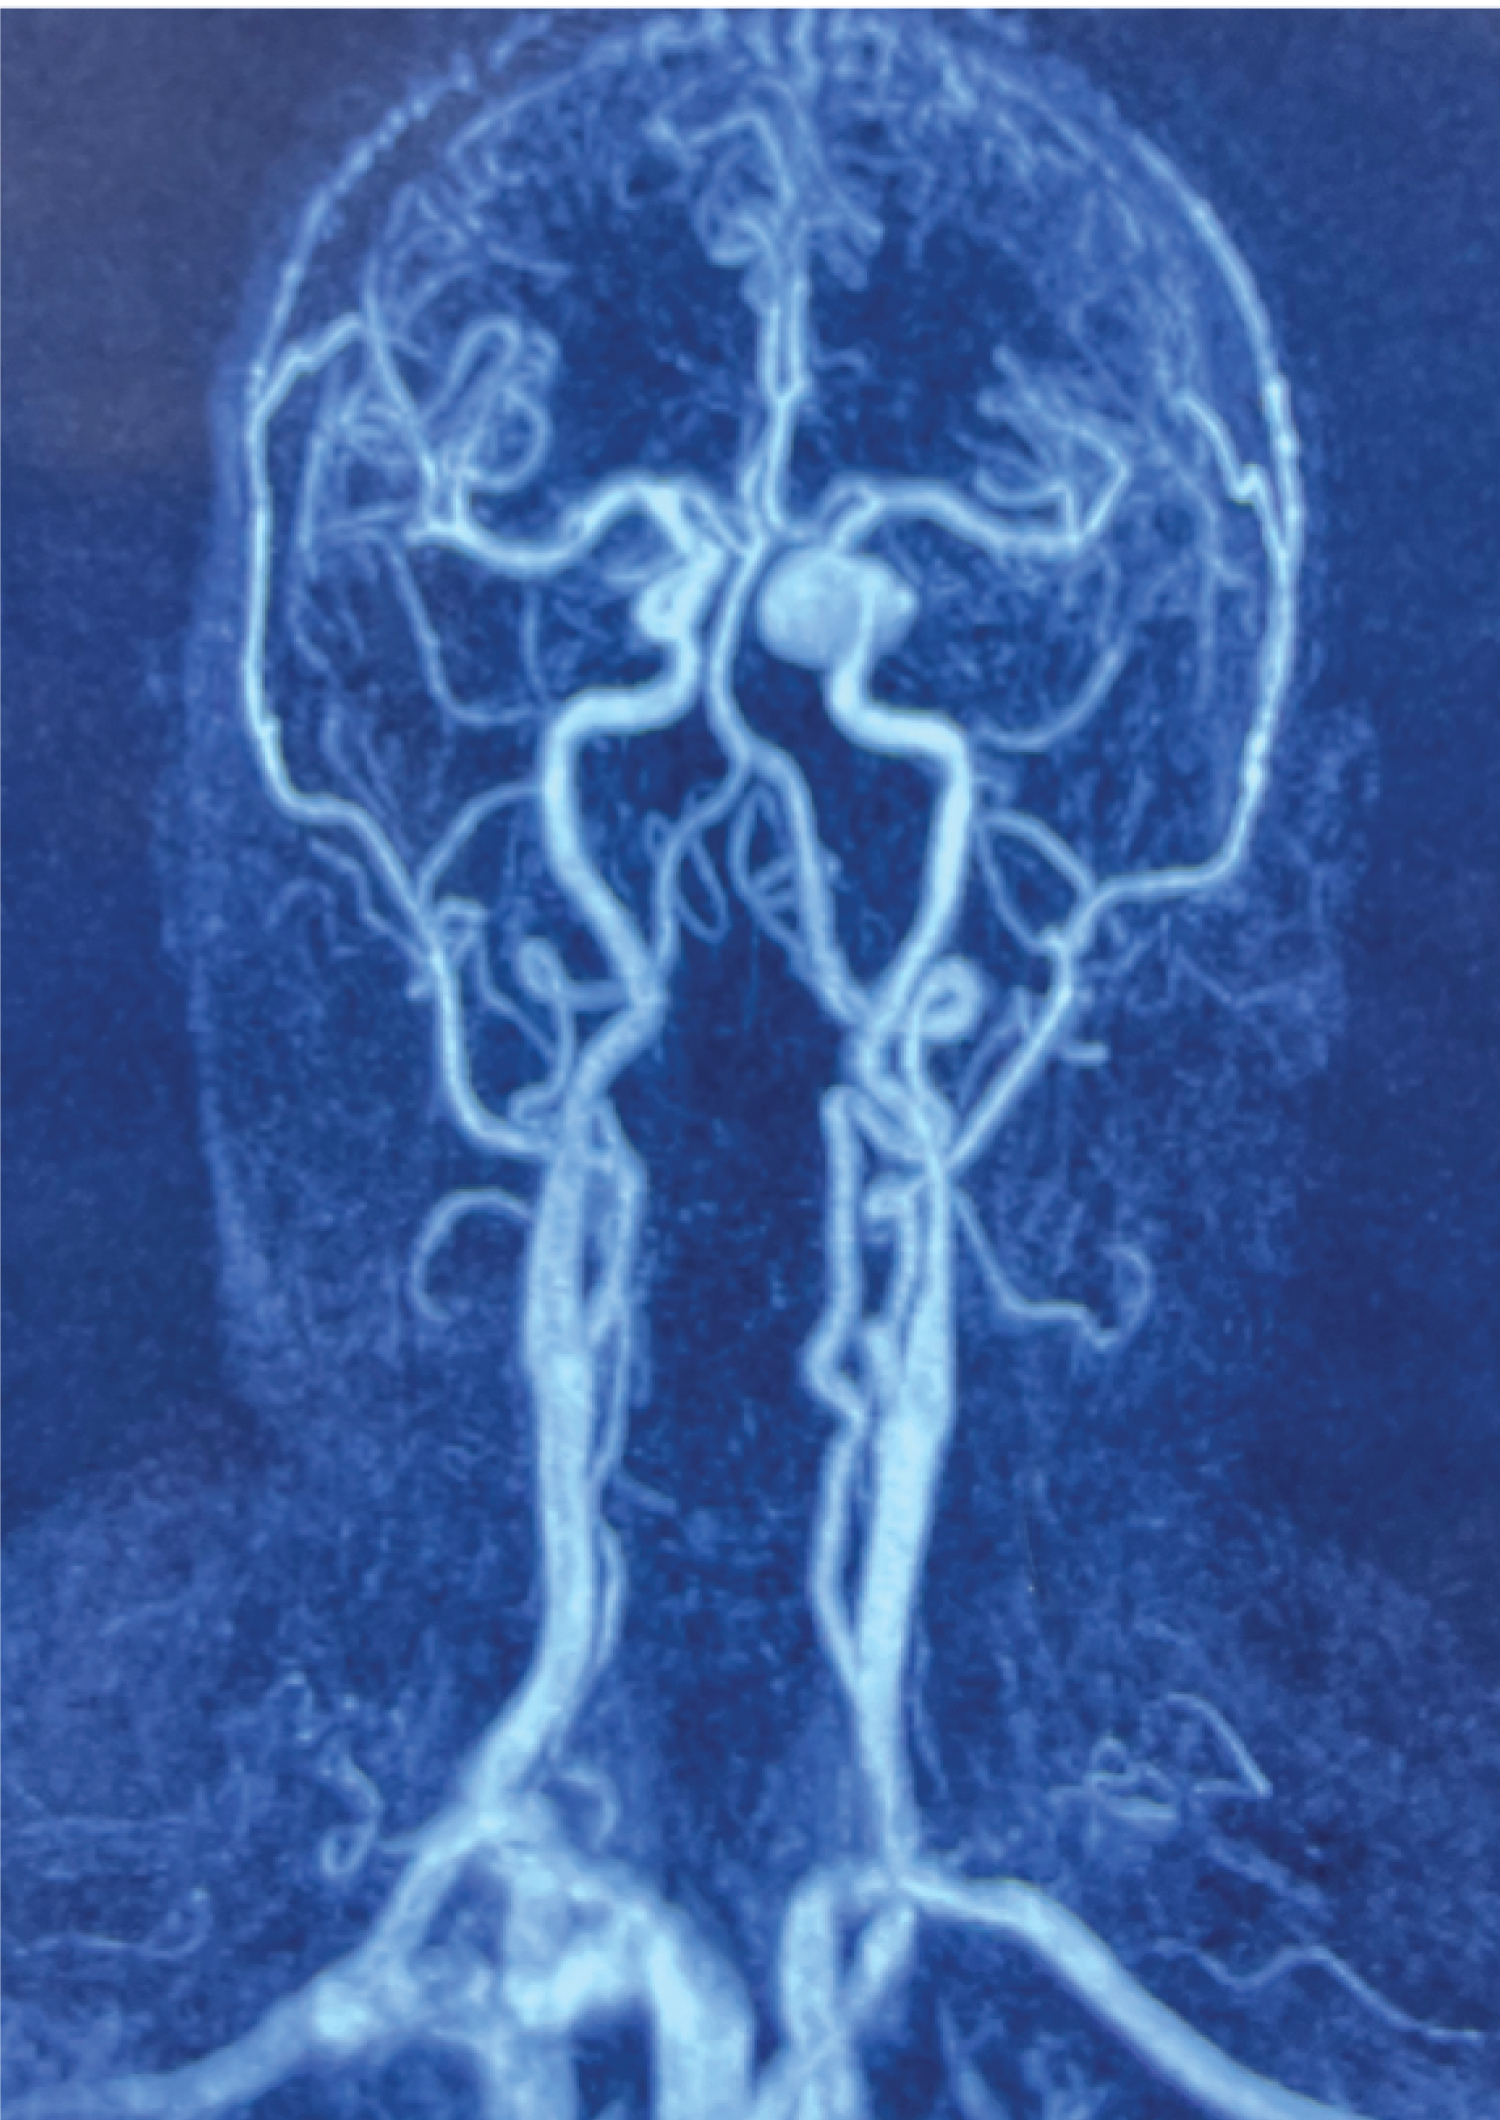

The second case is a 60-years-old female patient with double vision and headaches for the last 6 months. The cerebral CTA scan showed a giant 3 cm aneurysm of the left cavernous segment ICA (Figure 2). In the same fashion as in the first case we dissected the ICA in a surgery under general anesthesia. Three days after the first surgery we occluded the ICA distally to the aneurysm in the segment proximal to the ophthalmic artery in an awake surgery under local anesthesia. The postoperative cranial CTA shows again a complete thrombosis of the aneurysm and the regular signal of all arteries distal to the clip (Video 4).

Figure 2: Intracavernous left giant ICA aneurysm. The ICA was occluded distal to the aneurysm in an awake surgery. View Figure 2